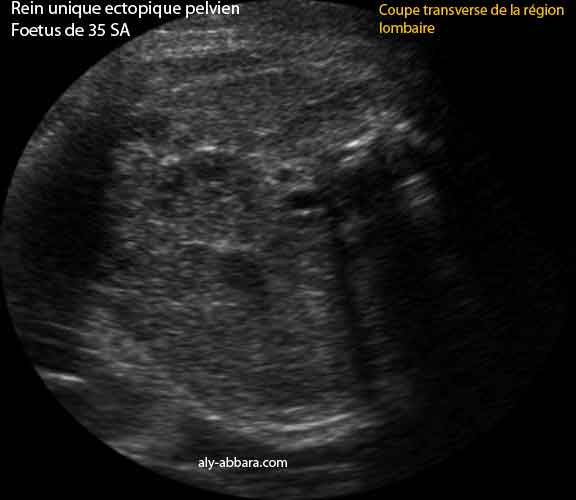

Rein unique ectopique pelvien ou agénésie rénale unilatérale avec ectopie

Fœtus âgé de 35 SA

Trois images échographiques montrant d'abord l'absence de structures rénales dans les deux loges rénales lombaires classiques, puis le Doppler couleur met en évidence de l'absence des deux branches artérielles rénales habituelles ; enfin, sur les coupes transverse et oblique du tronc au niveau de la région lombaire et pelvienne, on remarque la présence d'un rein unique médiane situé directement devant l'aorte abdominale et derrière la vessie.